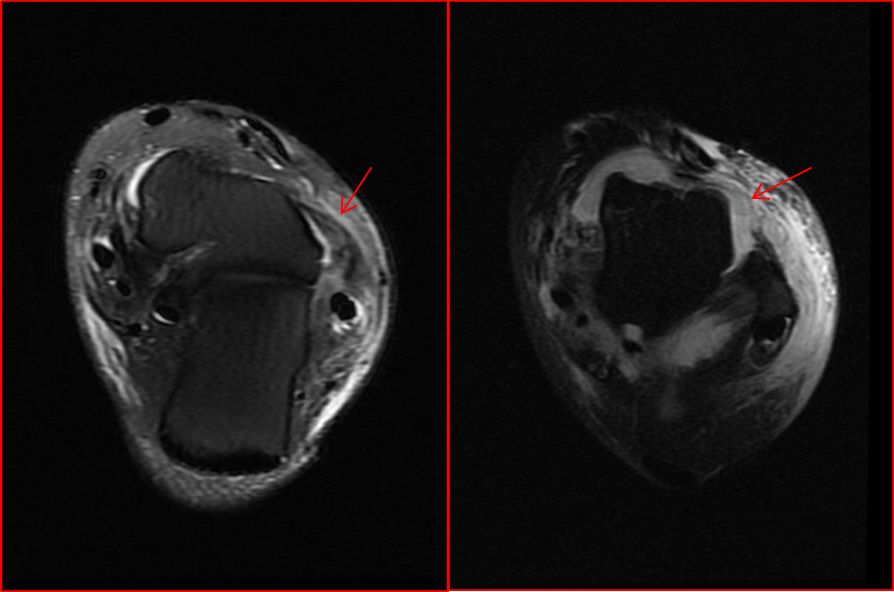

患者扭伤后到医院就诊,X线平片为首选检查方法,观察有无骨折脱位,但是对于韧带损伤无法显示。核磁共振对软组织损伤有高分辨率、多序列、多平面成像、无辐射、评价快速等优点,成为骨关节系统韧带及软组织损伤的重要检查方法。根据损伤程度,韧带损伤可分为I-IV度损伤:I、II度损伤较轻,为韧带纤维轻度撕裂伤,可以保守治疗,III度损伤为韧带纤维大部分断裂,IV度损伤为韧带完全断裂,III、IV度损伤会造成关节失稳,经保守治疗效果不明显的,应该考虑手术治疗。

上图为距腓前韧带III度及IV度损伤